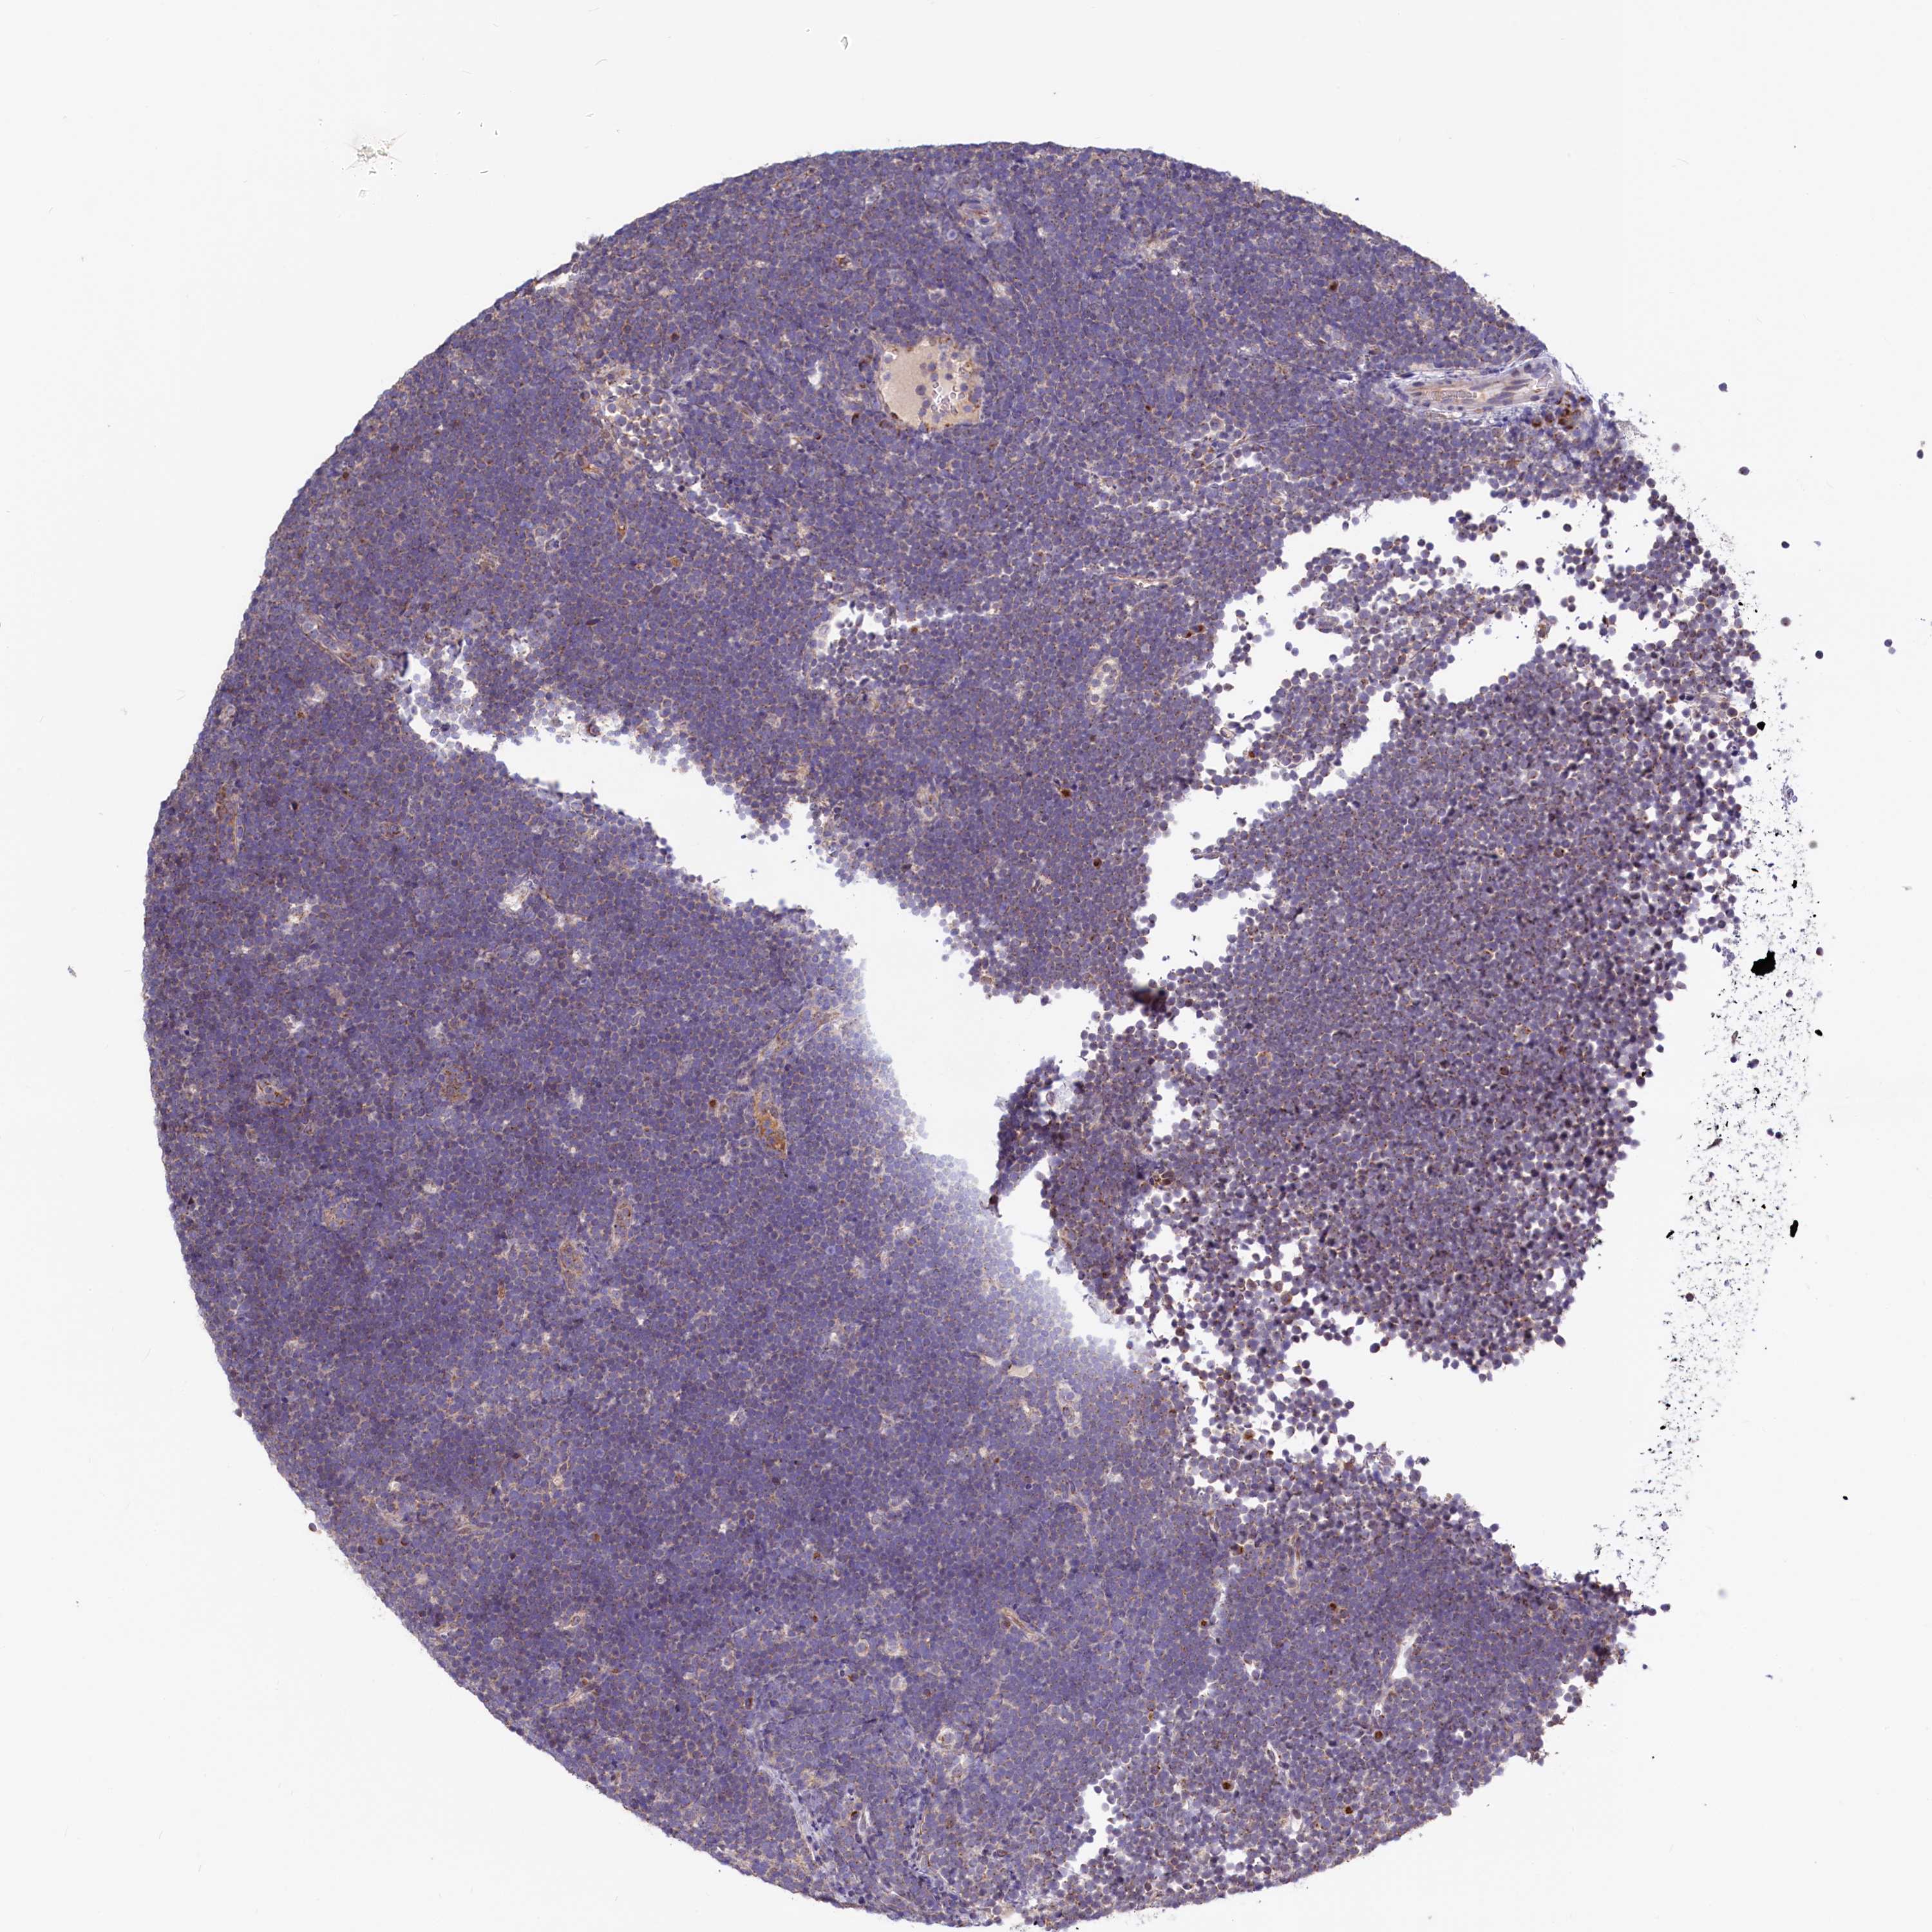

CANCER LYMPHOMA Show tissue menu

LYMPHOMA - Protein expressioni

A mouse-over function shows sample information and annotation data. Click on an image to view it in a full screen mode. Samples can be filtered based on level of antibody staining by selecting one or several of the following categories: high, medium, low and not detected. The assay and annotation is described here.

Each image is clickable and will lead to virtual microscopy that enables deeper exploration of all samples and also displays staining intensity scores, fraction scores and subcellular localization as well as patient and tissue information for each sample.

Antibody HPA040213

Hodgkin's disease, NOS

Malignant lymphoma, non-Hodgkin's type, High grade

Malignant lymphoma, non-Hodgkin's type, Low grade